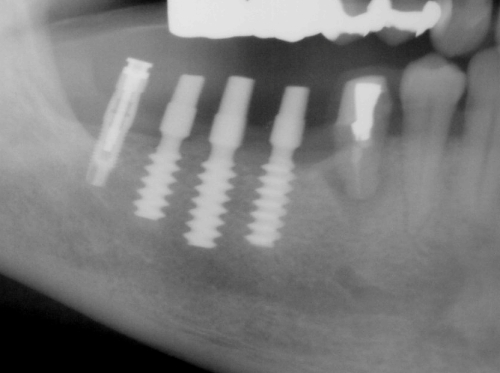

パノラマ写真